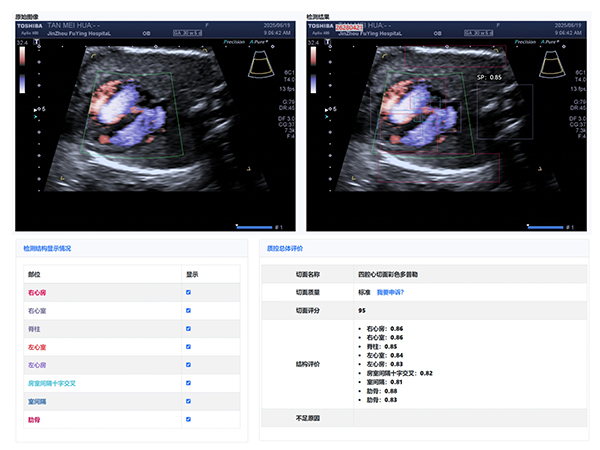

大赛汇聚了超声科全体医生,他们在产科超声领域各展所长。本次大赛引入了产前超声AI智慧云平台作为评分系统。

该平台利用先进的图像识别技术,对参赛的NT、I级、Ⅱ级、Ⅲ级产科超声图像进行精准分析与评分,确保了比赛的公正性与准确性,也体现了医院在医疗领域智能化、精准化的探索与进步。

经过激烈的角逐,年轻医生陈昱在NT产科超声图像评比中,凭借对NT精准的测量荣获第一名,展现出新生力量的专业风采;王斌医生在I级产科超声图像评比中,以精湛技术和对细节的精准把握摘得桂冠;刘芳医生的Ⅱ级产科超声图像作品,凭借清晰的图像质量和准确的诊断信息脱颖而出;Ⅲ级产科超声图像作品的评比竞争尤为激烈,李杭医生以微弱优势获得第一名。

大赛主持人超声科邵雪竹主任总结:“值此中国医师节举办图霸大赛,意义非凡。这不仅是技术的较量,更是我们交流学习的平台。通过活动,我们相互学习,共同提高,为患者提供更优质服务。AI智慧云平台的引入,标志着我院产科超声诊断迈向智能化、精准化。”

锦州市妇婴医院(妇幼保健院)作为锦州市权威产前诊断中心,肩负着对辖区内产前筛查机构(超声产前筛查切面完整率和超声产前筛查切面标准率等)的质控数据进行质量控制,超声科本次大赛初步尝试利用人工智能AI大数据技术开展质量控制与评价,取得了良好的效果。我们将以此为契机不断完善,促进全地区产前筛查服务的标准化、同质化。